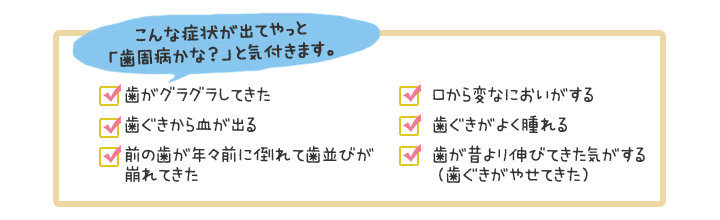

「歯肉が腫れて、膿がたまって、歯がグラグラしてきて、しばらくして歯が抜けてしまうんでしょう?」と。

おっしゃる通り歯周病は歯肉が腫れてきますし

膿もたまります。